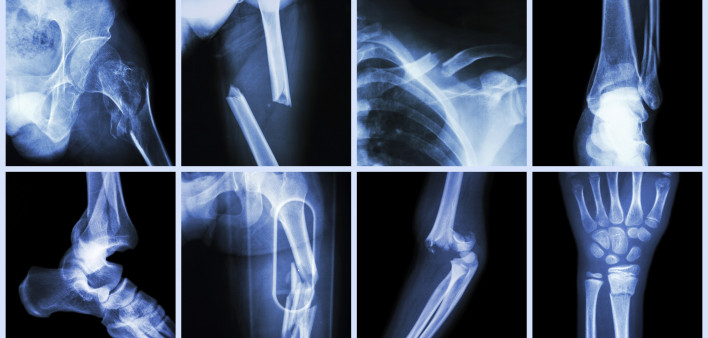

In this analysis, 158 HIV-positive women and 86 HIV-negative women across the menopause spectrum agreed to undergo whole-body dual-energy X-ray absorptiometry (DXA) and quantitative computed tomography (CT) scans to assess their bone mineral density (BMD).

Despite this, the HIV-positive women’s bone mineral density was lower on almost every measure. Women with HIV had lower areal BMD (5% to 9% lower) at the lumbar spine, femoral neck (hip bone joint), total hip and radius (forearm bone). Volumetric BMD was more than 15 points lower at the L1 lumbar vertebra and 20 points lower at the hip. Osteopenia, the precursor to osteoporosis, was also more common in women living with HIV compared with HIV-negative women at every site in the body, though in most cases the difference did not reach the threshold for statistical significance.

Low bone mineral density was more common in HIV-positive women who were at the end of perimenopause or entering menopause. Even after adjustment to account for race, body mass index, smoking, alcohol use, diabetes and hepatitis C status, HIV was independently associated with reduced areal and volumetric BMD at the lumbar spine and hip, among other sites. Overall, being HIV positive, postmenopausal and white were all associated with lower bone mineral density.